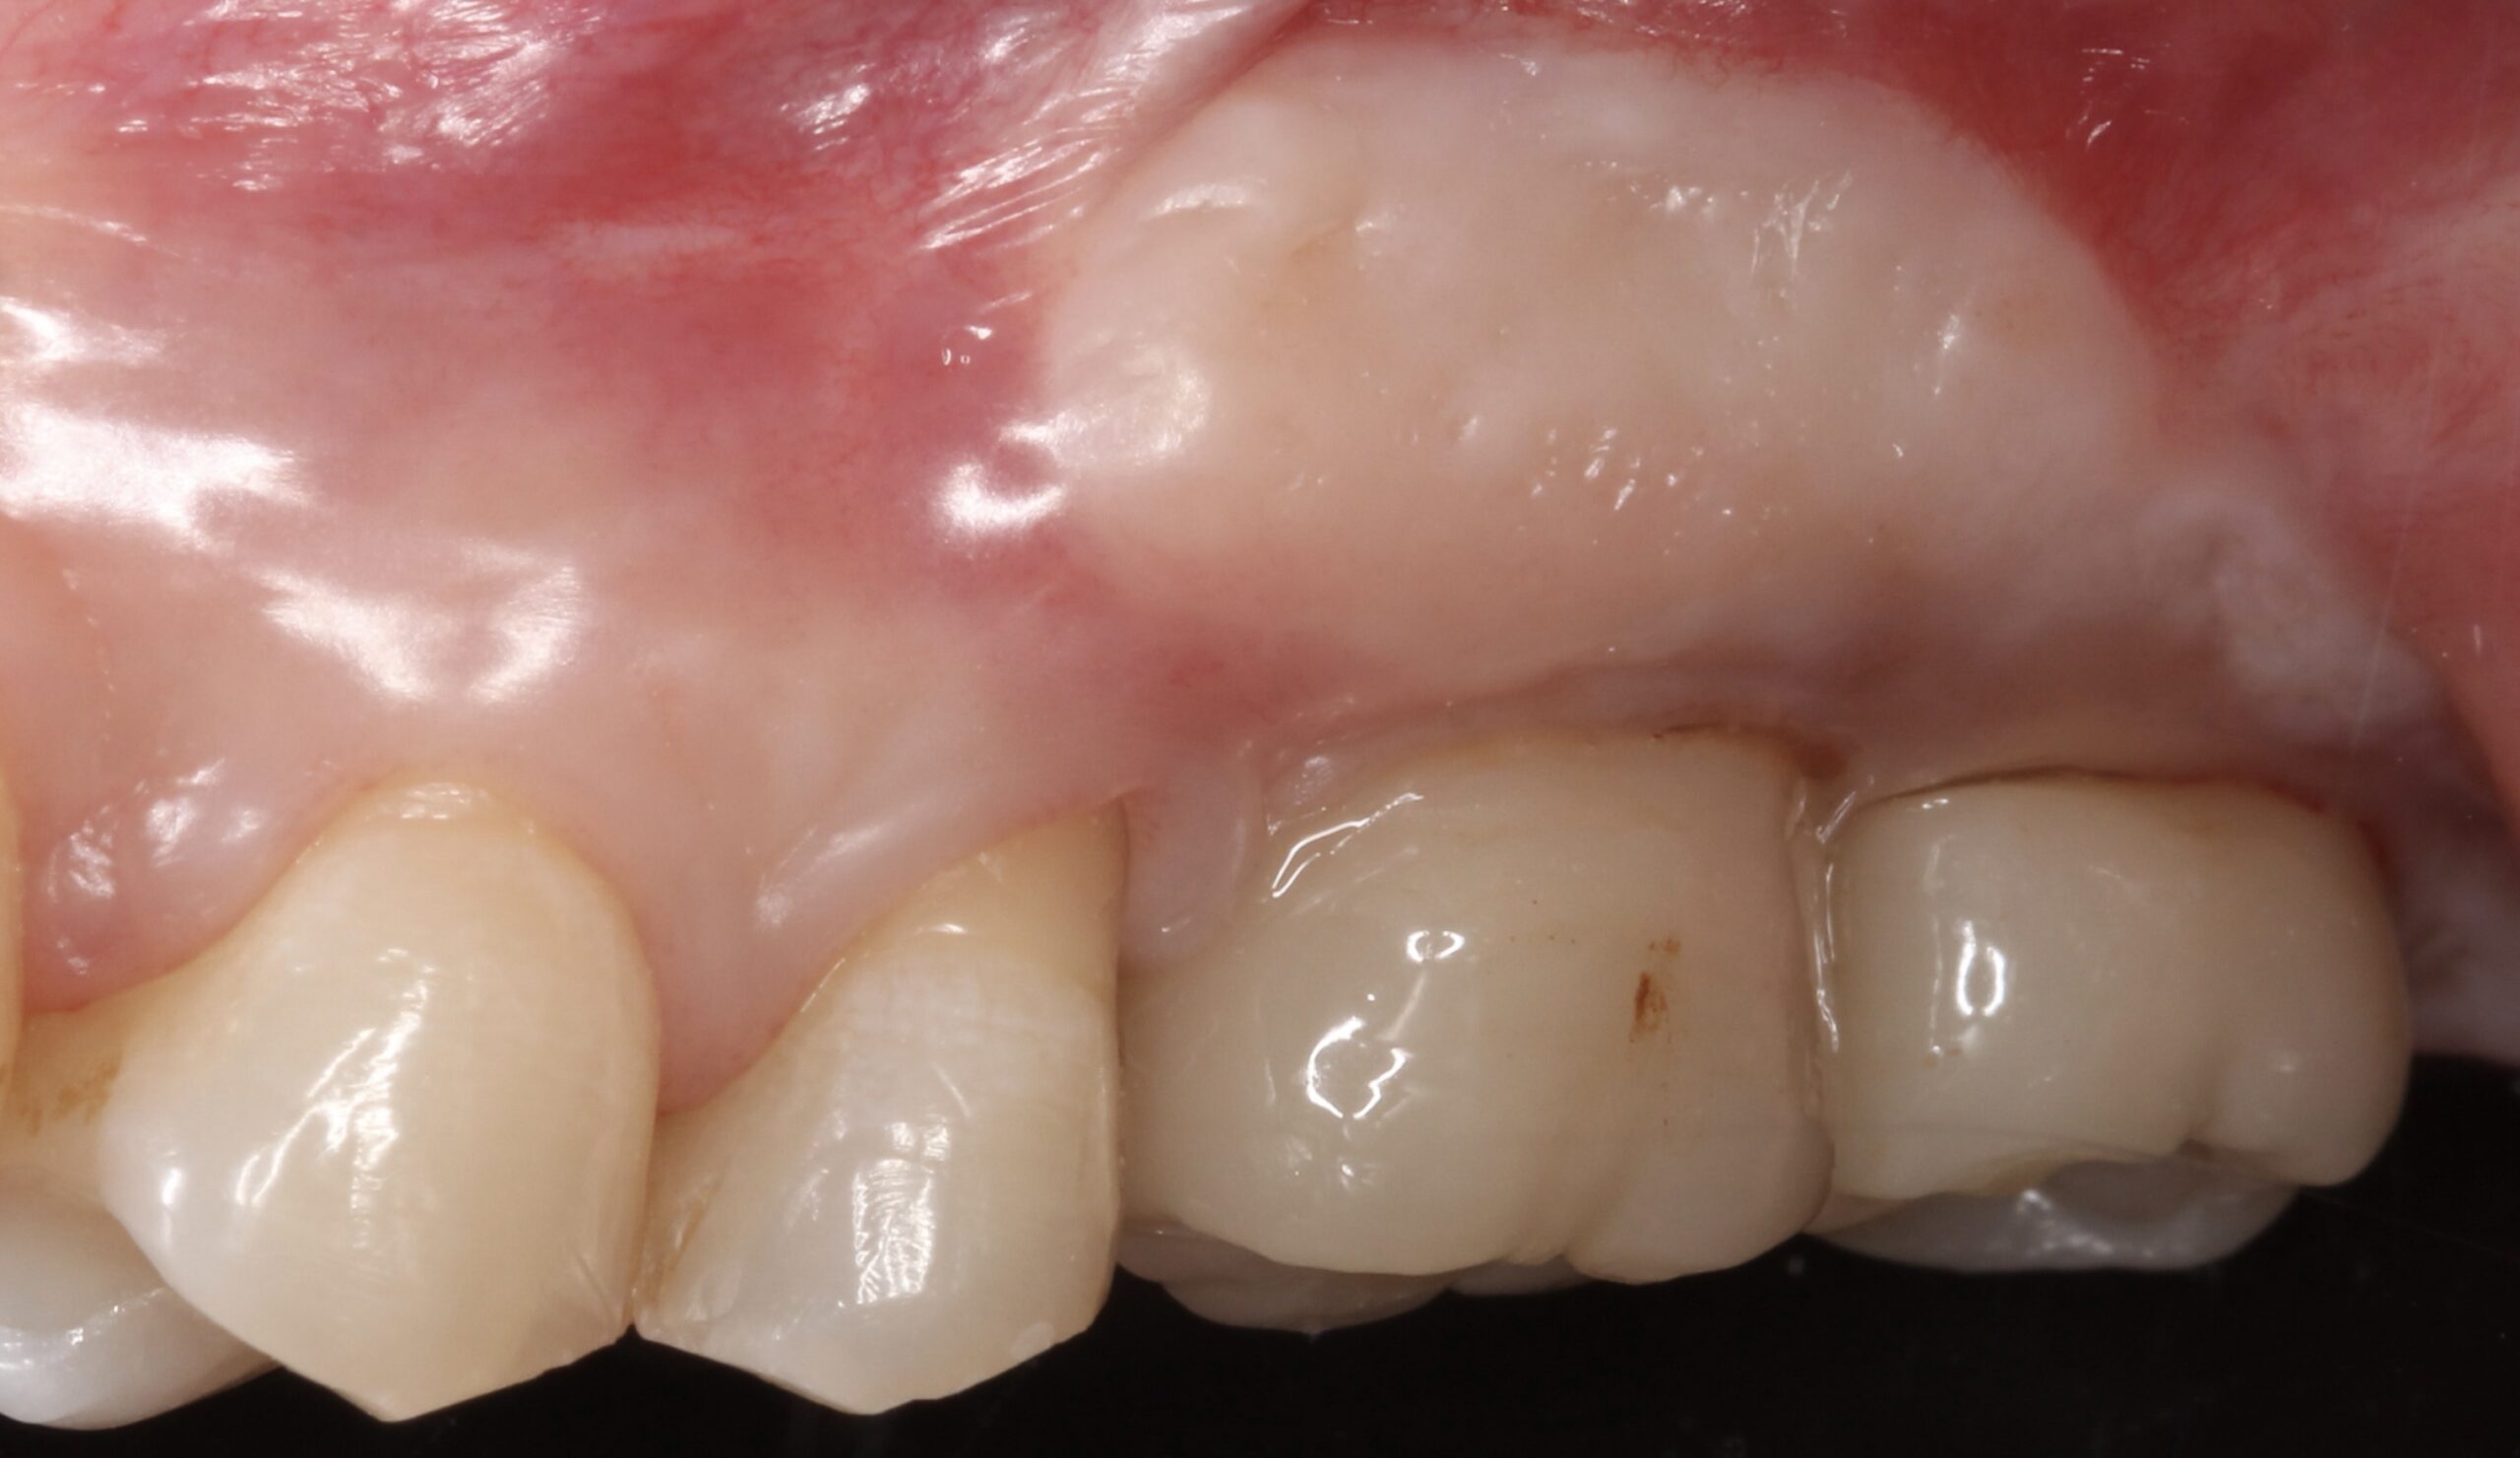

Figure 16.

Final crowns at 26 and 27 two years after loading.